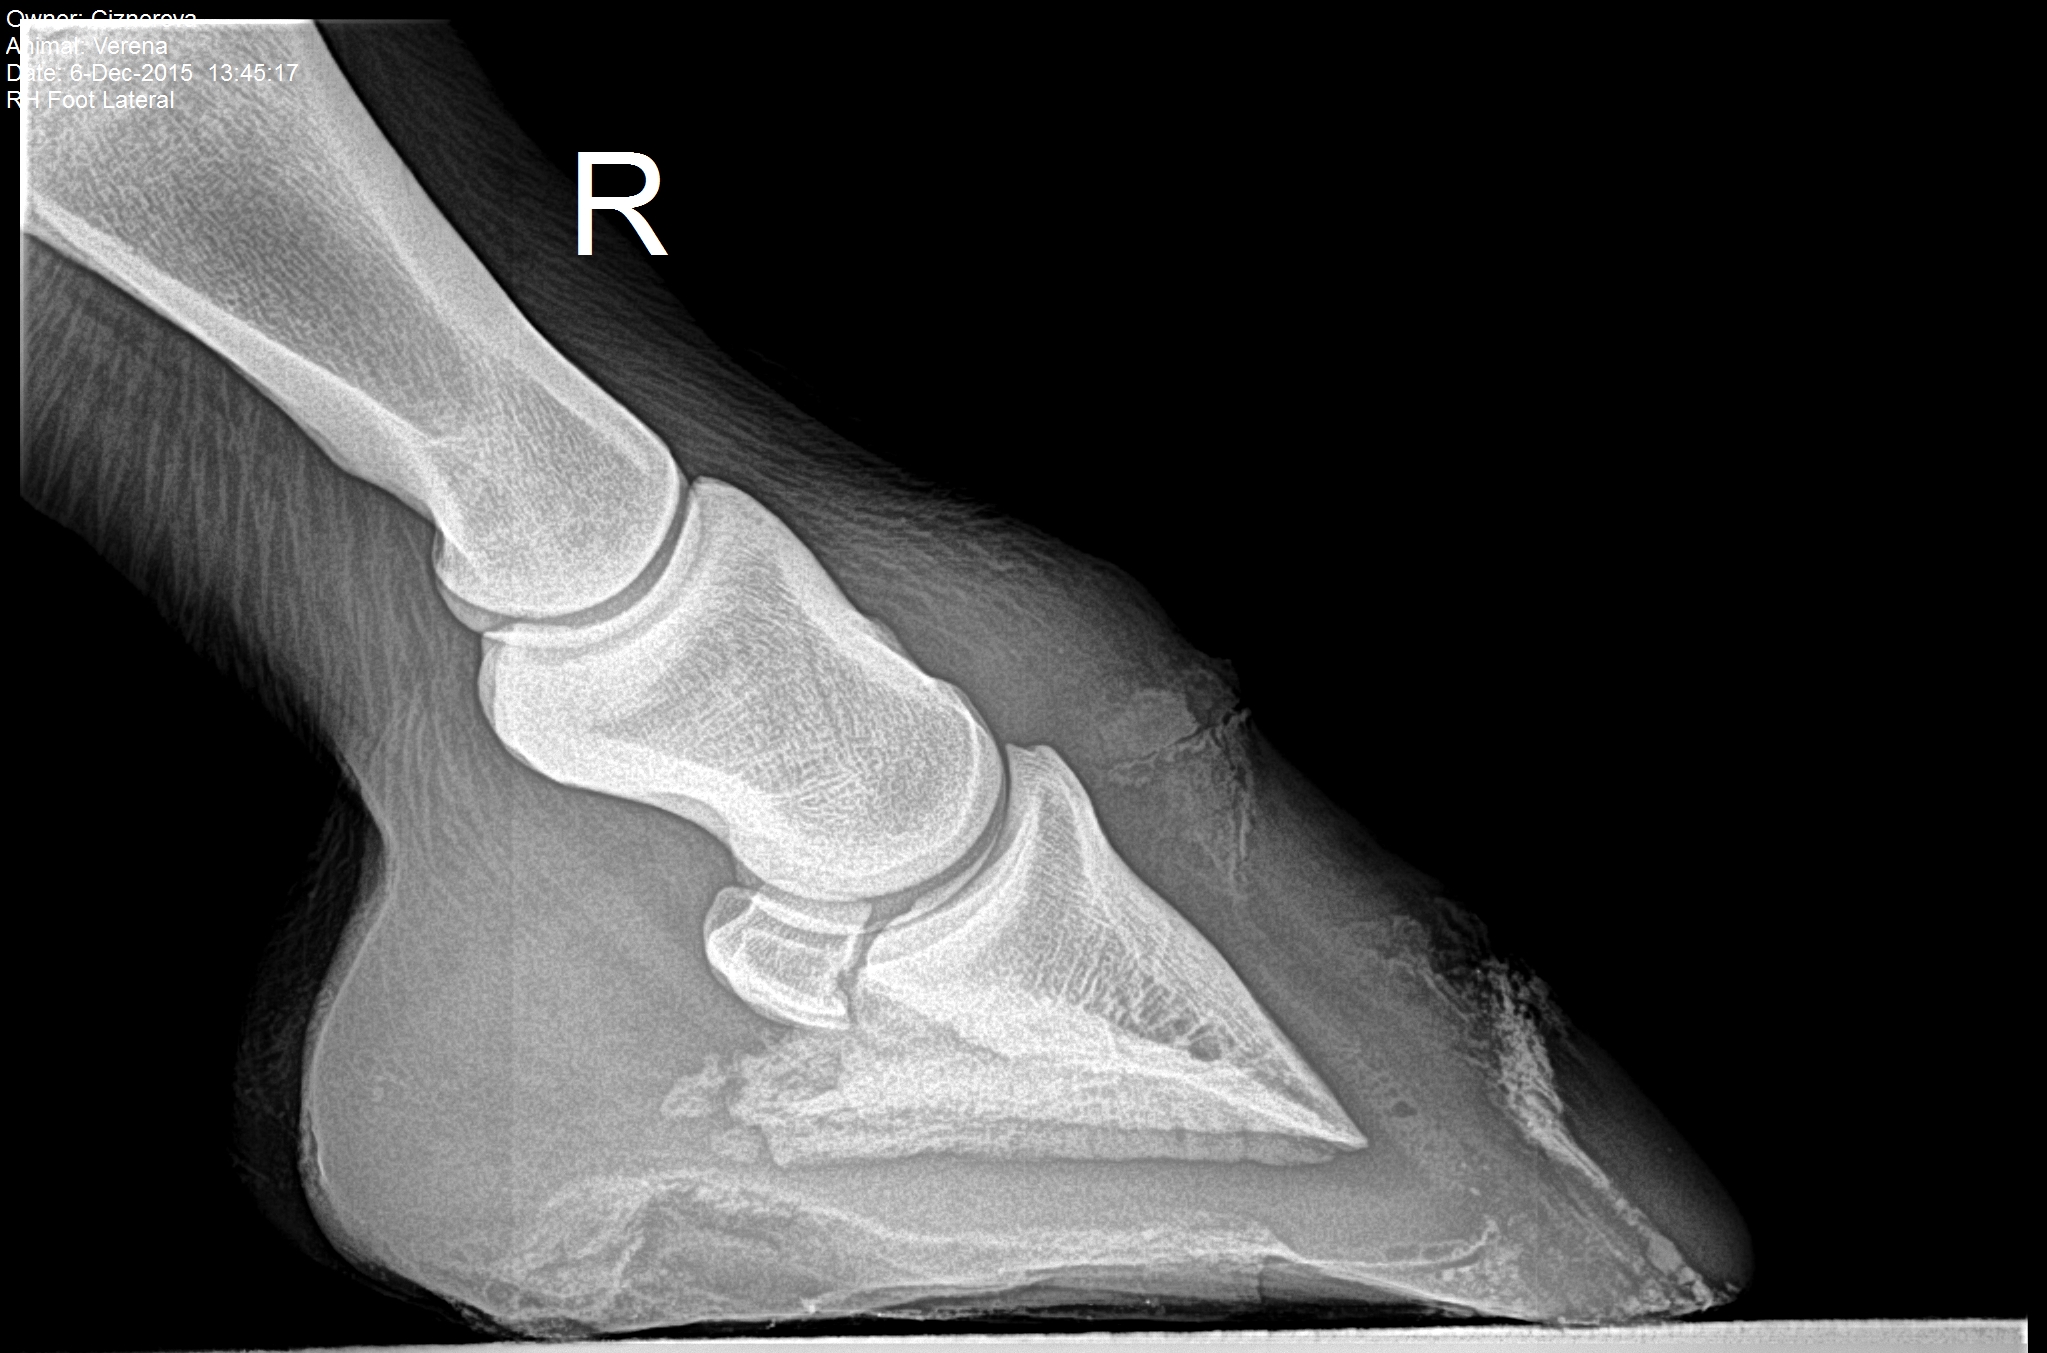

Na naše pracoviště byla zakoupena pro potřeby hipatrické praxe,vedené MVDr.Lenkou Vajsovou,nová přímá digitalizace RTG obrazu,která v obtížných terénních podmínkách zabezpečuje rychlé zhotovení kvalitního RTG snímku.

DR-Tech Equine Case

mobilní přímá digitalizace pro hipatrickou praxi

Jedná se o zařízení,kde flat panel DR-Tech je zabudován v mobilním kufru spolu s PC.Kufr pak společně s mobilním rentgenem tvoří kompaktní jednotku,přenosnou,vhodnou do terénní hipatrické praxe,pomocí kterého lze získat rtg snímky v excelentní kvalitě během několika málo sekund.

-špičková kvalita obrazu díky flat panelu DR-Tech FDXD 810